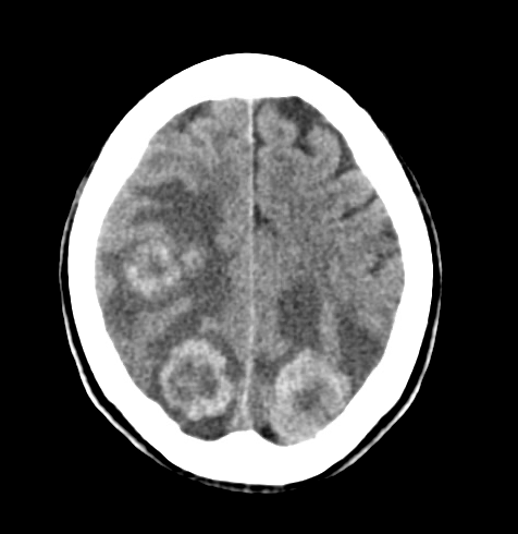

Case 4: A 67-year-old male presents in cardiac arrest via EMS. CT shows the following. What is the diagnosis?

Figure 9. Case 4’s CT scan. Image courtesy of Baylor Scott and White Memorial Hospital–Temple, Texas.

Answer: Multifocal hemorrhage.